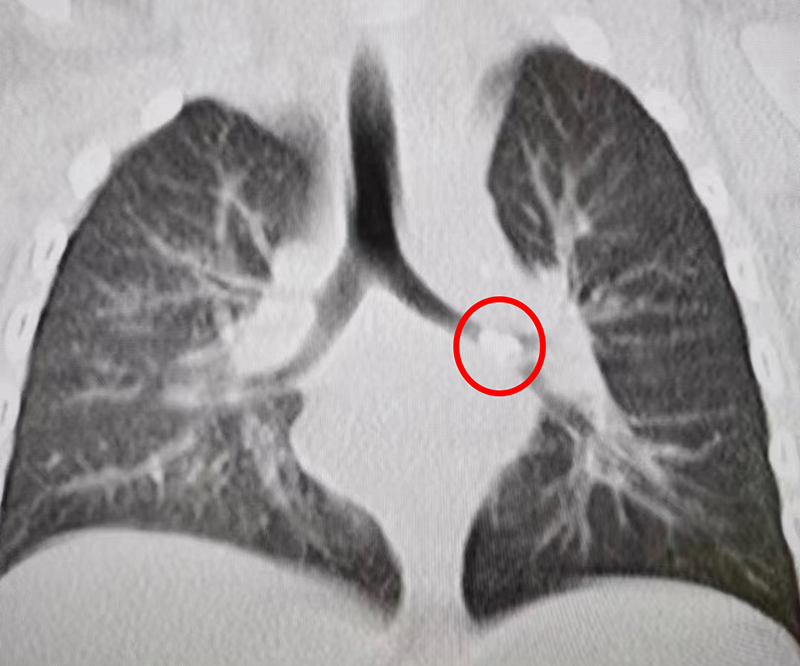

醫生詢問患兒是否有異物吸入嗆咳史時,家長均否認,并稱孩子以喝奶、米糊為主,也沒有發生過嗆咳,但根據患兒的臨床表現,醫生仍認為有氣道異物,立即安排了胸部CT檢查,結果讓家長大吃一驚。原來,患兒的左側主氣道被一異物卡住,并出現阻塞性肺氣腫,如果不及時將異物取出,可能出現進行性呼吸困難與呼吸衰竭,甚至危及生命。

經術前縝密討論及模擬,在多學科協同配合下,手術醫生小心地松解嵌頓異物,然后用異物鉗將異物順利取出。原來,讓患兒連續咳嗽兩天的異物是一塊0.5*0.5cm大小的白色脆骨。家長回憶,患兒近日確實喝過骨頭湯。異物取出后經進一步觀察與治療,患兒已順利出院。